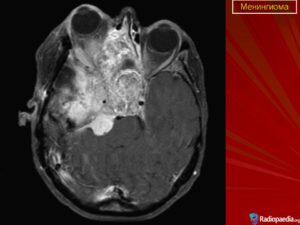

- Компьютерную томографию (КТ) — точность результата составляет 90%;

- Магнитно-резонансную томографию (МРТ) – с точностью 85%;

- МРТ – определяет наличие новообразования;

- КТ – определяет задействованность костной ткани и опухолевых кальцинатов;

- МРТ – магнитно-резонансная томография является абсолютно безопасной, поэтому часто используется для проверки состояния пациента на ранних дооперационных стадиях и в период послеоперационного восстановления. МРТ помогает распознать рецидив заболевания, а также определить наличие опухоли при объеме всего в несколько миллиметров.

- Компьютерная томография – обследование проводится с контрастным усилением. КТ признаки указывают на наличие опухоли, а также помогают выявить природу новообразования, не прибегая к дополнительным диагностическим процедурам. Злокачественная опухоль имеет тенденцию накапливать контраст в своих тканях, что и становится очевидным на снимке КТ.